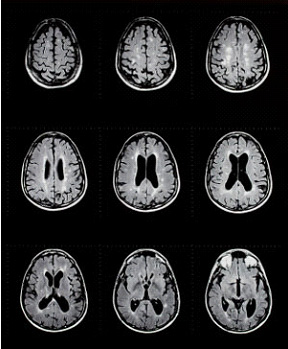

图片源于网络

多发性硬化是一种慢性疾病,侵犯中枢神经系统(脊髓,视神经和脑)。常见症状是肢体麻木,更严重比例会出现瘫痪和失明。根据多发性硬化症基金会的数据,现有350,000~500,000确诊病例,每周有200人被诊断为多发性硬化症。